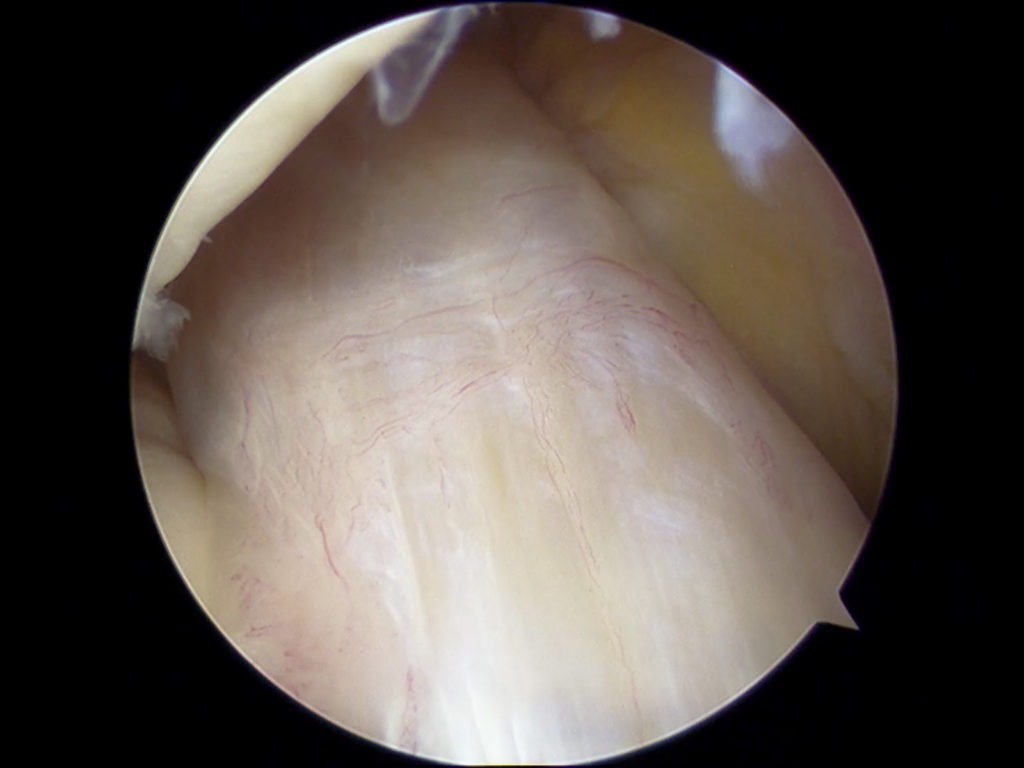

The procedure itself is usually carried out under general anaesthetic and involves making two small incisions on the knee and inserting a small arthroscope (camera) into one incision to see inside the knee joint, while instruments are inserted into the other.